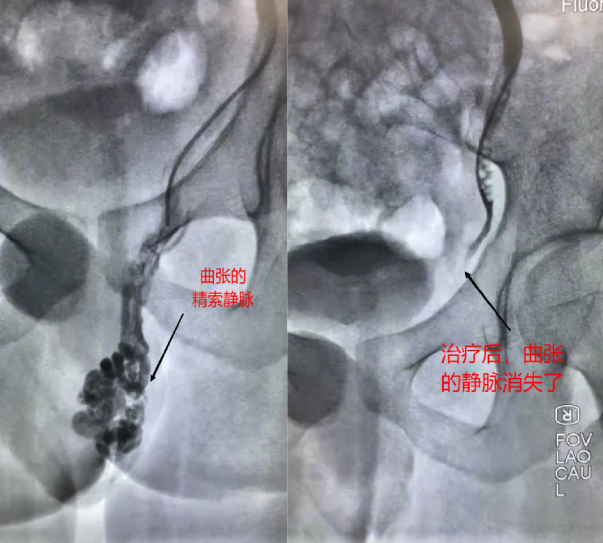

颜鹏副主任医师接诊患者后进行初步检查,发现小王站立位即可触及左侧阴囊存在迂曲、扩张的静脉团,咳嗽时会明显增大。这是精索静脉曲张的典型表现。为了病人能够最快速的康复,赶上应征检查。颜鹏副主任医师在完成对小王的术前评估后,即刻行介入手术,对左侧精索静脉行栓塞治疗,经肘正中静脉穿刺,顺着血管直达曲张的精索静脉,用药物直接栓塞病变血管。仅仅针眼大小的创口,不到30分钟就完成了手术。再一看阴囊,嘿,曲张静脉团消失了。小王开开心心地走下了手术台,第二天就办理了出院。

精索静脉曲张是精索内蔓状静脉丛的异常扩张、延长和迂曲。是男性常见病,多见于20~30岁的青壮年,多发生在左侧,原因与性腺静脉的解剖特点有关。症状包括阴囊或睾丸持续性或间歇性坠胀感、隐痛或钝痛。站立时可见患侧阴囊及睾丸低,严重者可见并触摸到蚯蚓团块状曲张静脉。颜鹏副主任医师介绍:“精索静脉曲张的危害在于影响睾丸的温度和正常的生精功能,引起男性不育。目前常规治疗精索静脉曲张手术方法是通过外科手术结扎精索静脉,不仅需要全身麻醉,而且存在创伤大,恢复时间长和体表疤痕等弊端。介入栓塞治疗从手臂的血管循路进入精索静脉,相对于传统精索静脉高位结扎,具有治疗更精准、创伤小、恢复快等优点。”术后,患者可步行离开手术室,基本没不适感觉,术后第二天就可出院。(介入血管外科三病区 钱潇博 颜鹏)